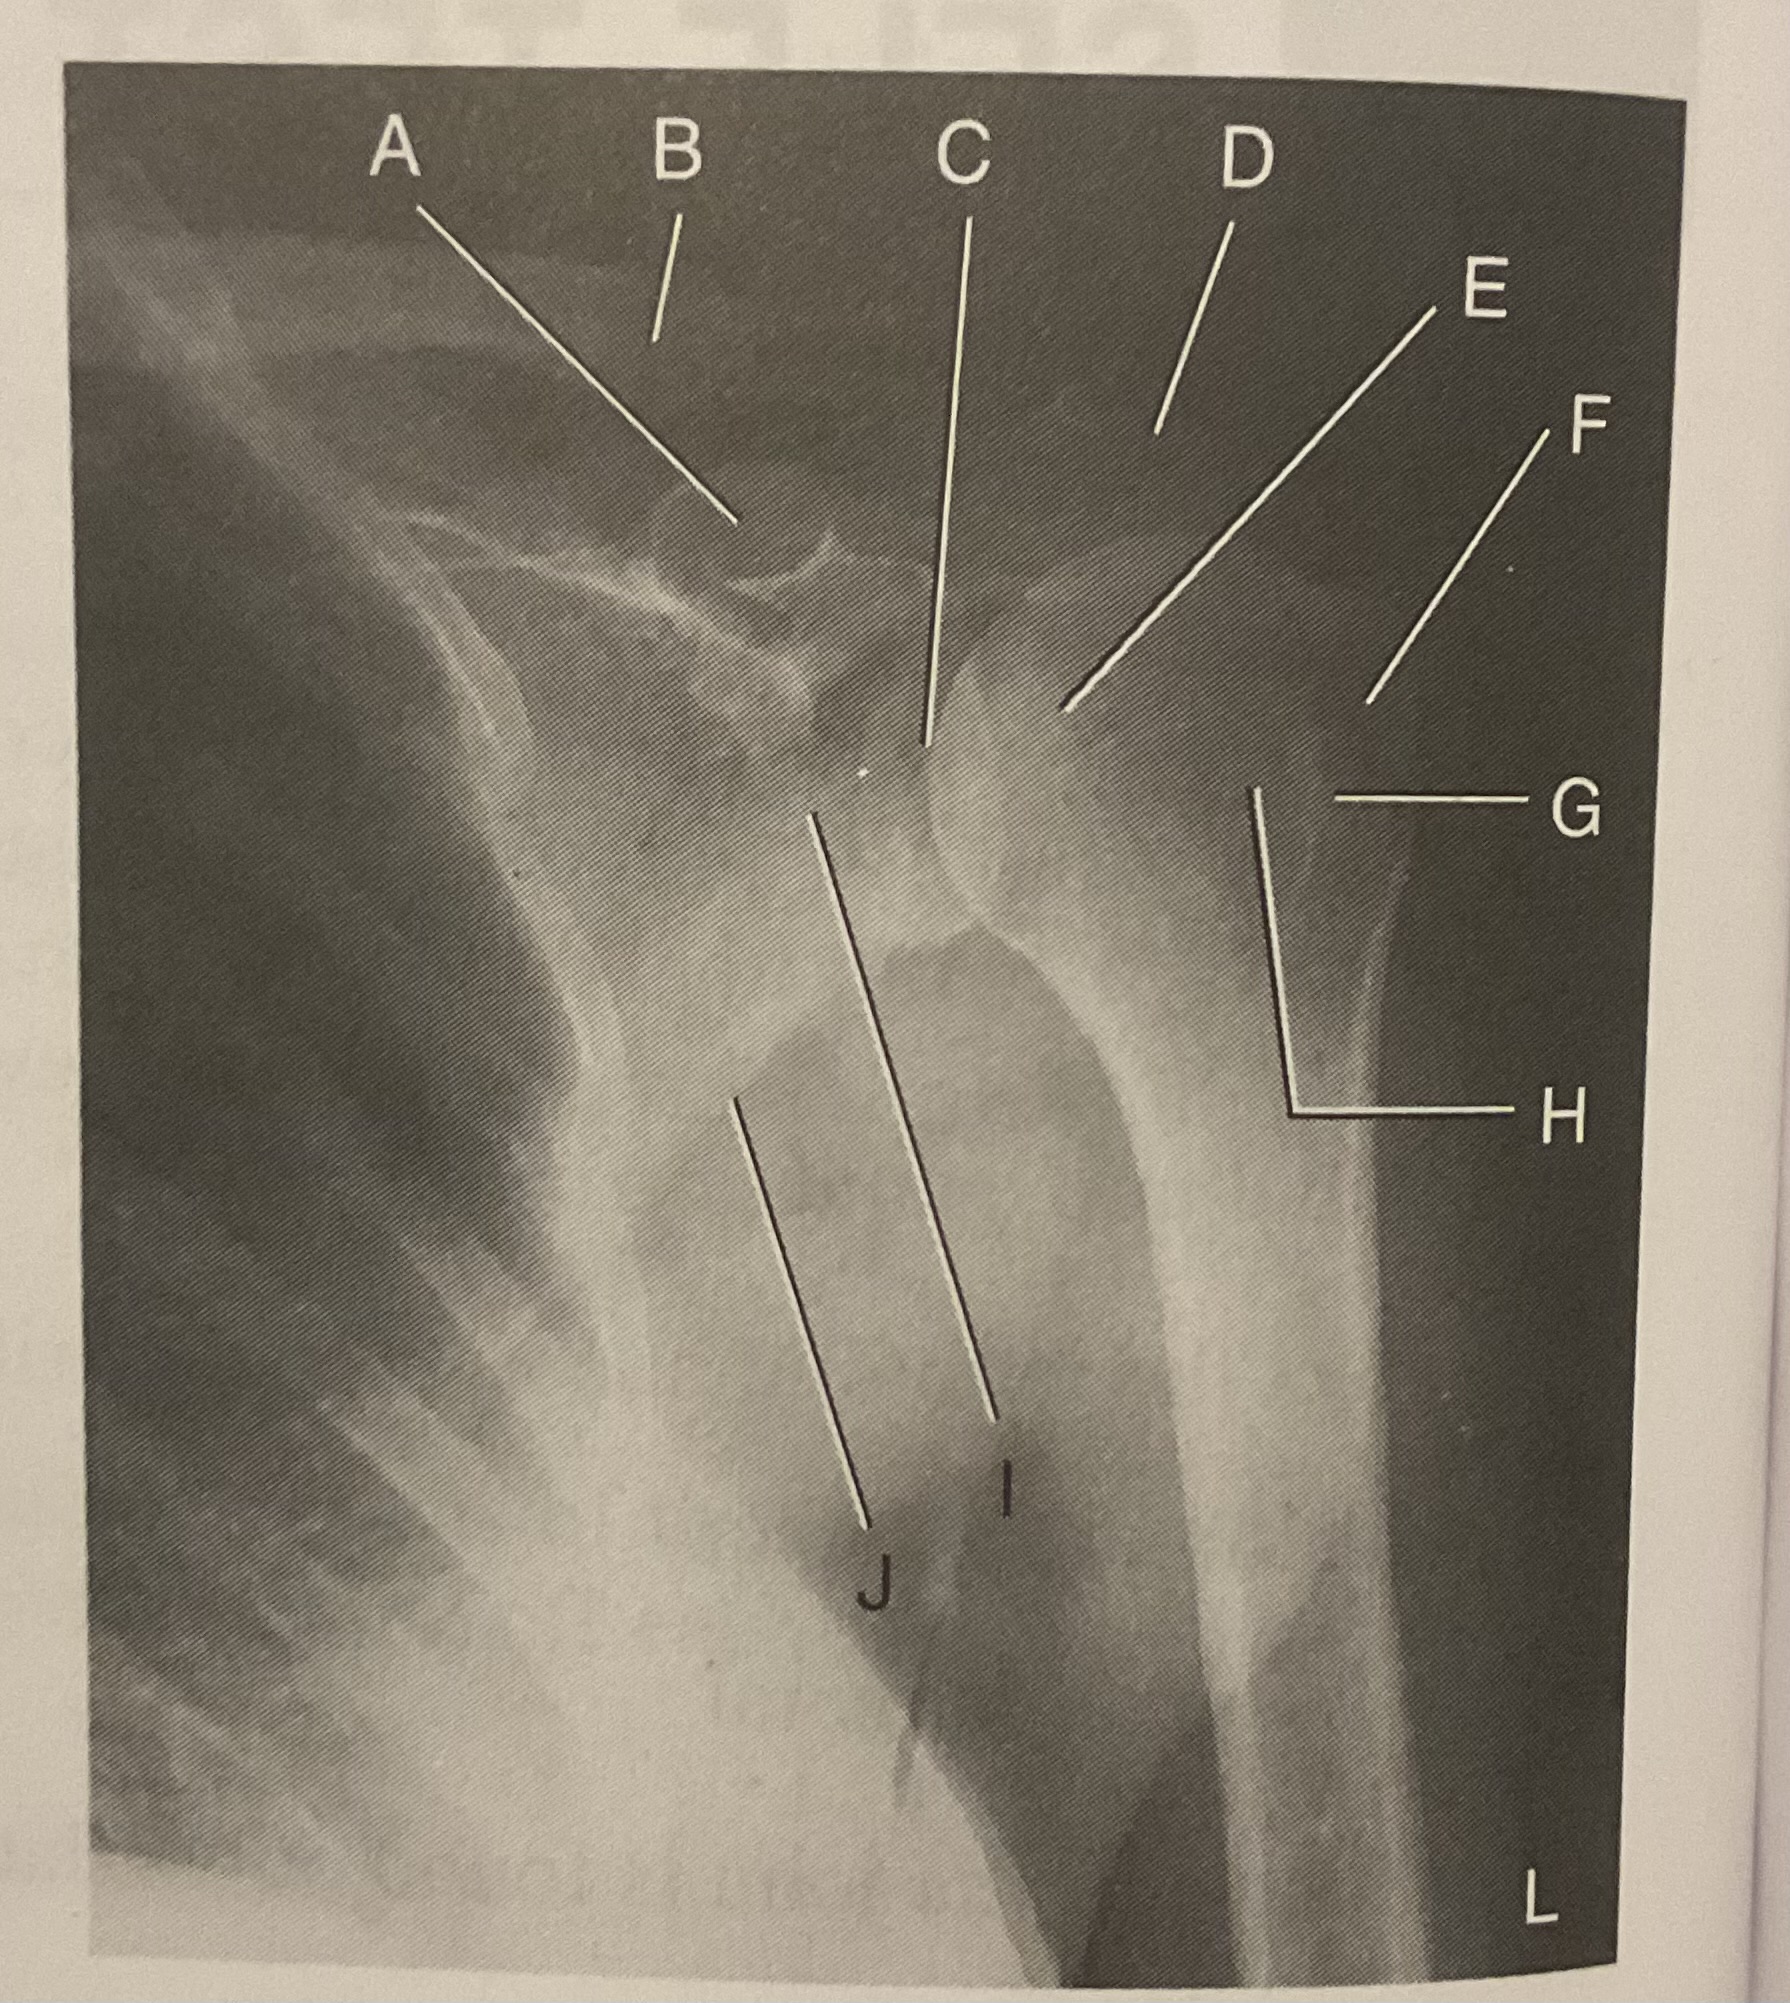

A?

Coracoid process

B?

Clavicle

C?

Scapulohumeral joint

D?

Acromion of scapula

E?

Head of humerus

F?

Greater tubercle

G?

Intertubercular sulcus

H?

Lesser tubercle

I?

Neck of scapula

J?

Lateral (axillary) border of scapula

What AP projection does this image represent?

External